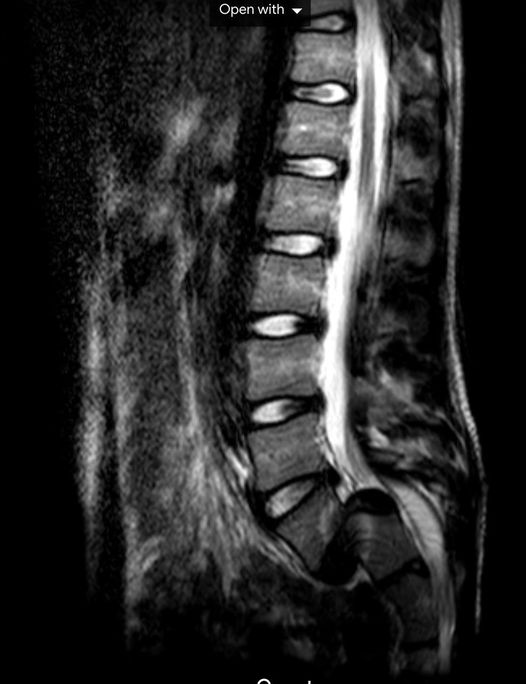

My 14 year old son had a small fall, and complained of immediate back pain and leg 'fuzziness'. Went to the doctor several times, was told to rest and gentle stretching etc. Third visit said 'it may be a slipped disc', we'll get you some physio (no physio happened). Eventually after several months we were finally referred to a paediatrician - who took one look at his back (first time anyone had actually 'looked' at his back), and said 'his back shouldn't look like that' and sent us for an urgent MRI.

Turns out my son had 'broken' his lower vertebrae in half and the whole spine had slipped forward into the Pelvis (Grade 4+ Spondylolisthesis). This was also crushing the nerves to his legs which were by now almost completely numb.

He had to have major spinal decompression and fusion surgery aged 15. Thankfully he's doing great now, but will have life-long back problems and restrictions. MRI-604f62...63db8.jpeg